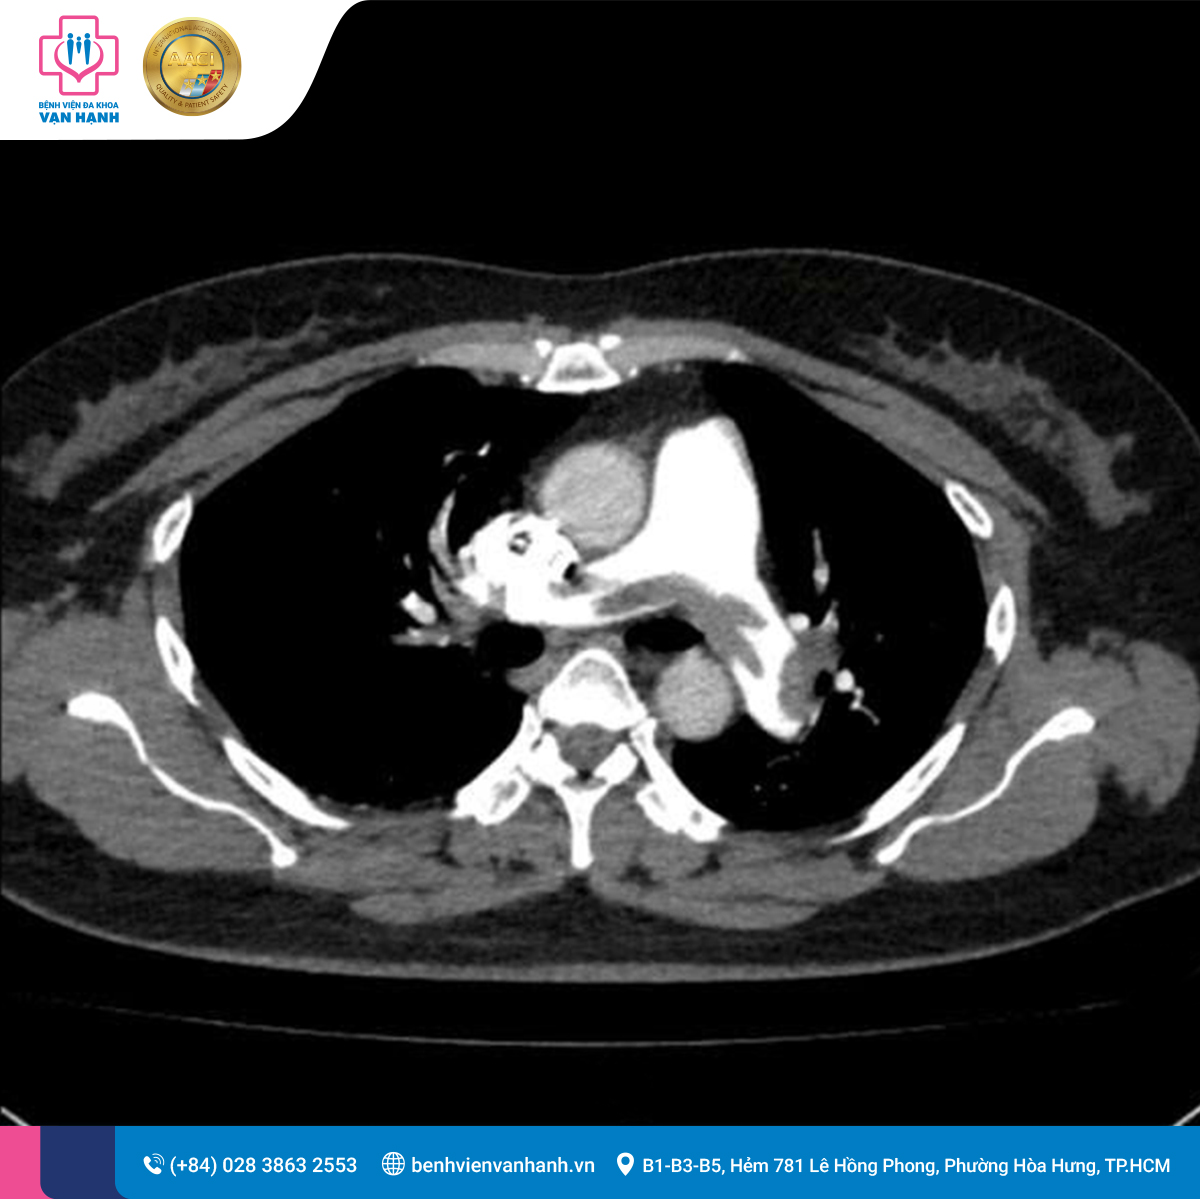

Trước tình trạng lâm sàng gợi ý sốc tắc nghẽn, bệnh nhân được chỉ định làm các xét nghiệm cấp cứu và chụp cắt lớp vi tính (CT Scan) động mạch phổi. Kết quả hình ảnh ghi nhận:

- Huyết khối bán phần nhánh động mạch phổi bên Phải (P) và Trái (T).

- Huyết khối tại các nhánh gian thùy dưới bên (T), các nhánh thùy trên (P) và nhánh A3 bên (T).

- Đặc biệt: Tắc gần hoàn toàn các nhánh gian thùy giữa và dưới bên (P).

Chẩn đoán: Sốc tắc nghẽn do Thuyên tắc động mạch phổi cấp (Pulmonary Embolism).